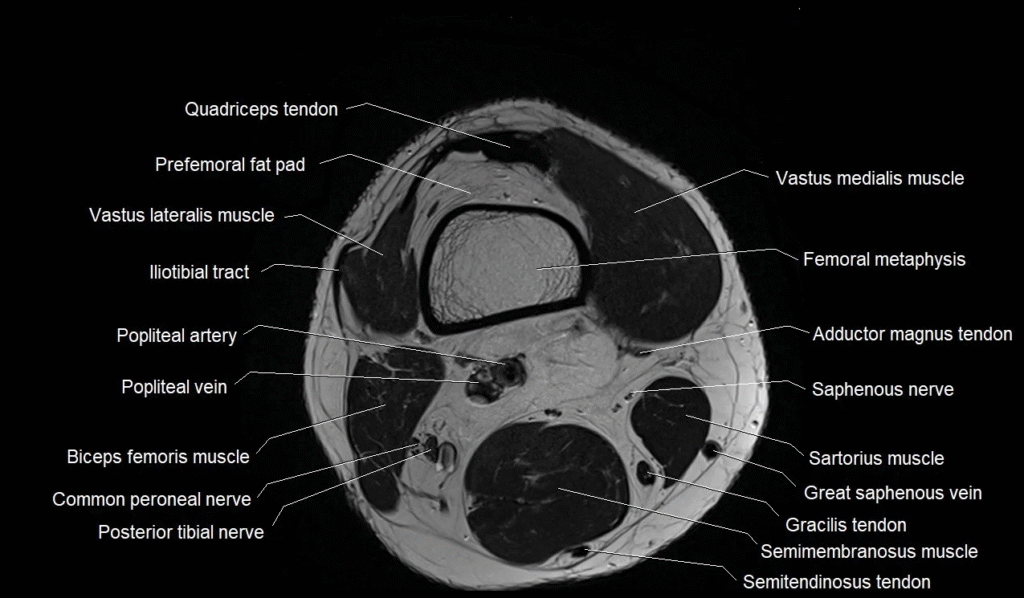

Understanding MRI Knee anatomy can help patients feel more confident when discussing knee pain, injuries, or treatment plans with their doctor. An MRI is one of the clearest ways to see what is happening inside the knee because it shows bones, ligaments, muscles, and cartilage in great detail. When you know what the doctor is talking about, it becomes easier to follow your treatment and understand the cause of discomfort.

The bones are the main framework of the knee, and an MRI shows them clearly. The knee is made up of three bones: the femur (thighbone), tibia (shinbone), and patella (kneecap). These bones form the structure that carries your body weight. On an MRI, doctors look for cracks, swelling, or signs of arthritis that may be causing pain or stiffness. Understanding how these bones sit and move can help you see why even small injuries can lead to big problems.

Cartilage is the smooth tissue that covers the ends of the bones so they can move without rubbing. In MRI Knee anatomy, doctors check for thinning or tears in cartilage because damaged cartilage is one of the main causes of long-term knee pain. When cartilage wears down, bones start to rub together, which leads to pain and swelling.

Ligaments are strong tissue bands that connect bones and keep the knee stable. The most well-known are the ACL and PCL, which help control forward and backward motion. An MRI can easily show whether these ligaments are torn, stretched, or swollen. Understanding these structures is helpful because ligament injuries often require long recovery times.

Tendons are another key part of MRI Knee anatomy. They connect muscles to bones and help the knee bend and straighten. The patellar tendon, for example, plays a major role in jumping and running. When tendons are inflamed or torn, the MRI helps doctors see how severe the injury is and what treatment may be needed.

The meniscus is a piece of rubber-like cartilage that acts as a shock absorber between the bones. There are two menisci in each knee, and they help protect the joint from wear and tear. On an MRI, a meniscus tear shows up clearly, and this is one of the most common findings in knee scans. Many knee injuries in sports or daily life involve the meniscus because it can tear during twisting or heavy movement.

Other soft tissues, such as small fat pads and joint lining, also show up on MRI. These parts may seem minor, but they play a big role in how smoothly the knee moves. When these tissues become irritated or swollen, they can create pain or make the knee feel tight.